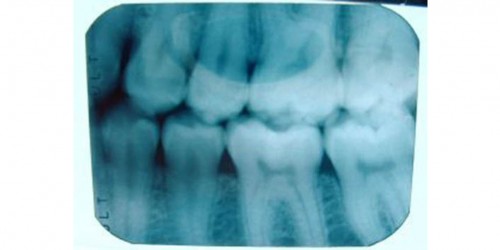

About a week ago, I noticed a hard bony like lump inside my mouth on my gum line under my second to last molar, so I went to the dentist. Nothing showed on the xrays so i was given amoxacillin 500mg 4 times per day for 7 days and told that if it wasn't better after 5 days to come back. This is day 4 and I now have the same bumps on my gum line under my tongue as well as a little swelling, but no pain at all. I noticed what looks like a pimple forming on the inside of my cheek in front of my top left molars and am becoming very worried. Please help

I think I have the same problem. Large, hard, boney lump on the lower front teeth. I went to the dentist today and he said it was nothing (or he couldn't be sure) and referred me to a doctor. I'm worried. May I know how yours turn out?